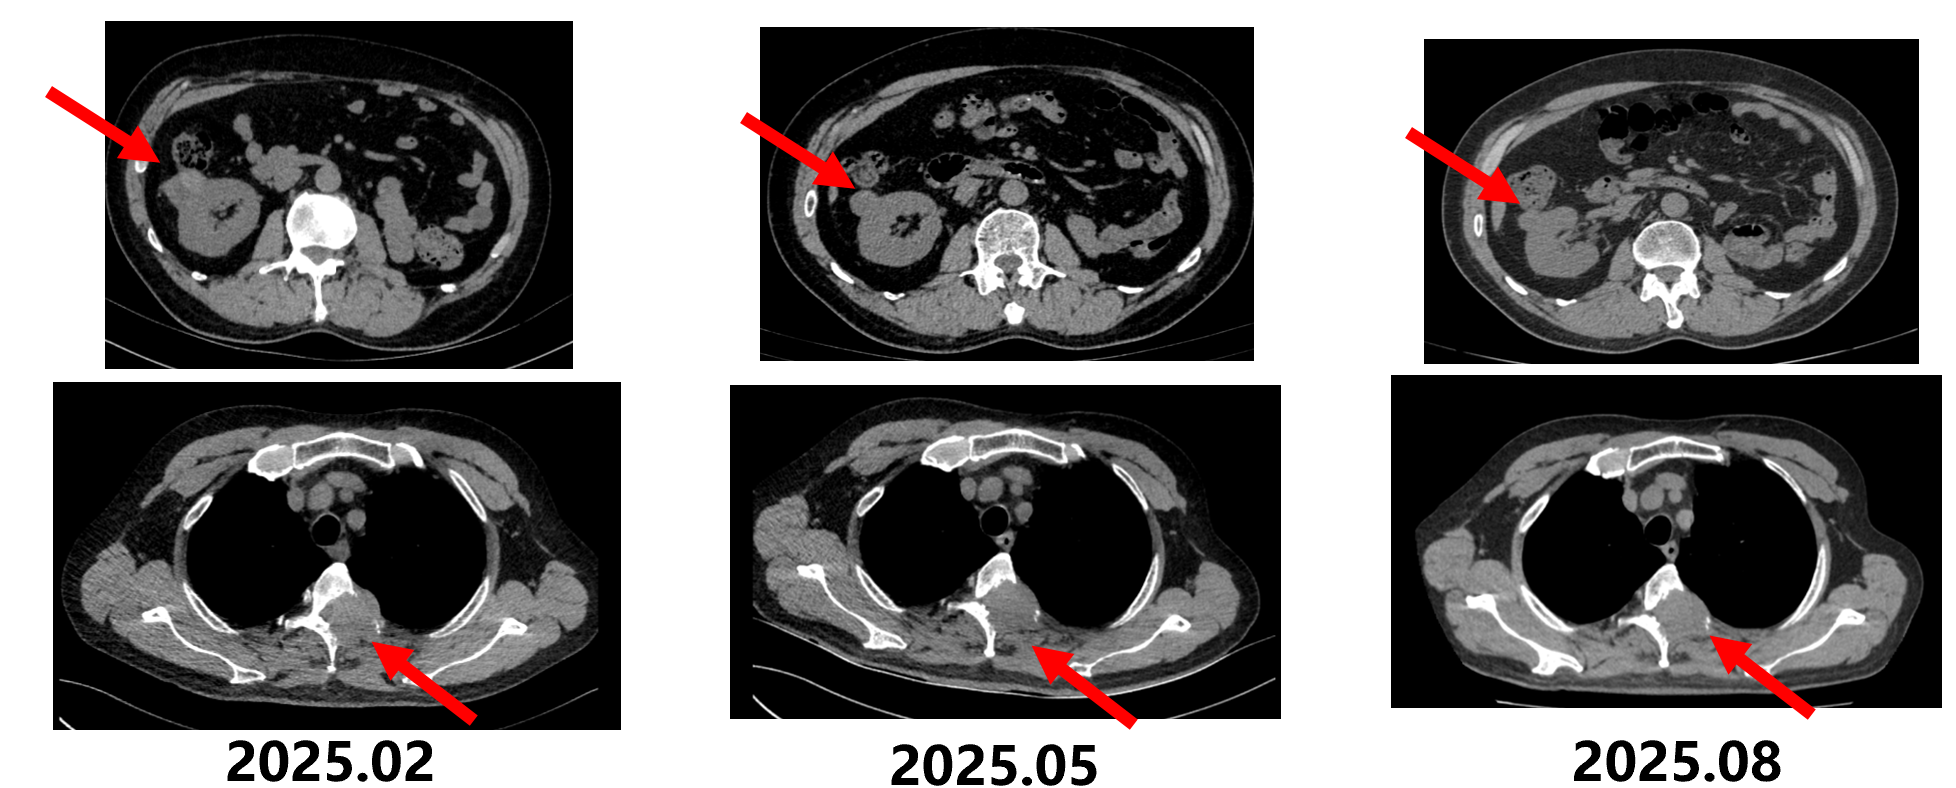

2025-2-27 CT示:Th3椎体左侧椎弓根及附件骨质破坏伴软组织肿块,较前增大,考虑转移。

2025.2.27:参加“一项评估IB-T101治疗晚期透明细胞肾细胞癌的安全性和有效性的开放、单中心研究”。患者2025.3.3 完成单采,3.27完成细胞回输。

完成细胞回输后当天,疼痛明显减轻,不需要止疼治疗。

副反应:回输当天发热1日,睡眠障碍 CTCAE分级2级,中性粒细胞计数降低 CTCAE分级1级。

肾病灶评估:PR。Th3椎体左侧病灶评估: SD。